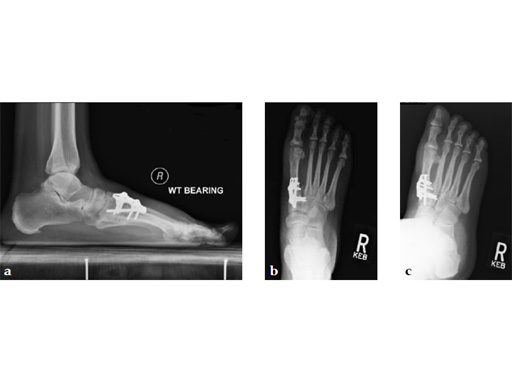

A 60-year-old woman with pes plano abductovalgus (flatfoot deformity).

Case provided by Andrew Sands, New York, New York, USA

The patient was treated by headless compression screw 6.5 tuber osteotomy, TMT plantarflexing osteotomy, and first TMT fusion a plate.